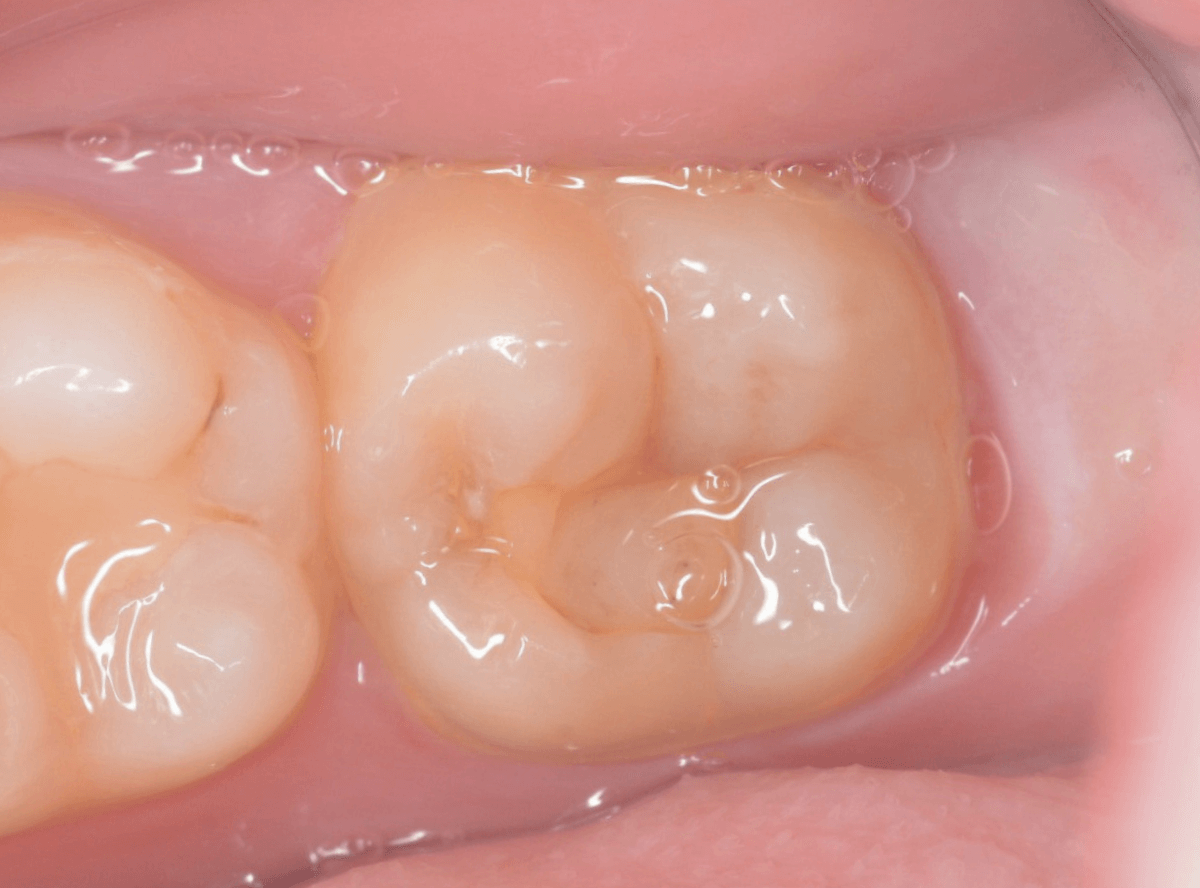

Case.13 問題なさそうなレジンの下で深い虫歯

他の歯の治療希望で来院された患者さんで、レントゲンで大きな虫歯が見つかった方です。

以前に虫歯を削って、レジンをつめる治療がしてあります。

表面を見る限り、特に問題はなさそうです。

レントゲン写真を撮影しました。

青い線が神経

黄色い線がレジン

赤い線が虫歯

です。

思ったよりも深い虫歯をレジンで埋めてあったようで、さらにその中が虫歯になっている状況です。

神経までかなり近い虫歯と思われます。

症状はありません。